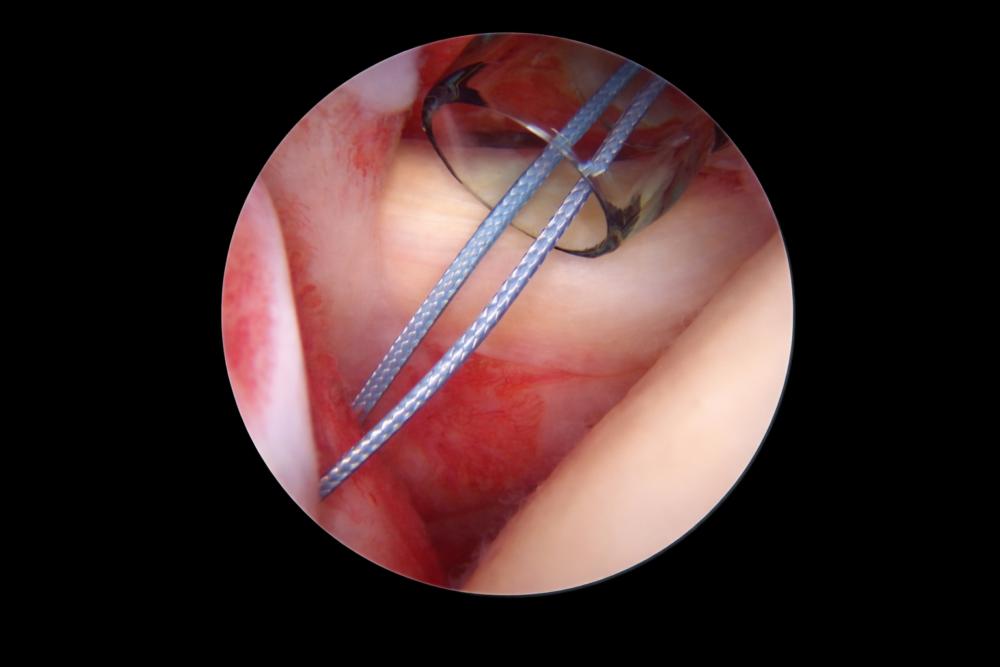

Needle-suture technologies

Engineered needle-suture systems designed for surgical performance.

Surgical sutures and closure systems

- Surgical sutures

- Tissue approximation

- Wound closure systems